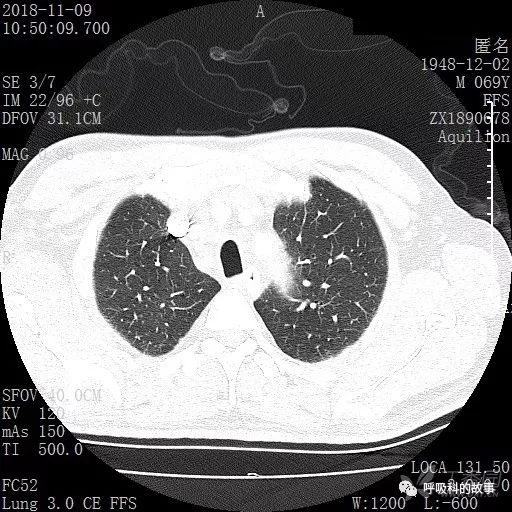

胸部增强CT示右肺门占位伴远端阻塞性肺炎,纵膈、右肺门、右侧颈根部、右侧腋下及肝门部肿大淋巴结。两侧胸腔少量积液。

肺窗CT